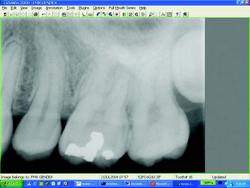

Digital Radiographic Technology

There are currently 2 different concepts of photon detection for direct digital image acquisition, the use of a solid-state image receptor or the use of a storage phosphor system. Many people think that Direct Digital Radiographic Technology means that you see an X-ray image immediately on a monitor, in fact the term direct digital refers to the direct acquisition of the image onto a receptor, like a CCD or a PSP device. Whereas the term Indirect Digital Radiographic Technology means that you take an existing X-ray film and convert it to digital after it has already been exposed and developed.

To capture a radiographic image you need an X-ray generator and a solid-state image receptor or more commonly referred to as a sensor. A sensor is just a silicon chip with an electronic circuit on it. There are two solid state sensor technologies on the market today:

CCD (charge-coupled device)

CMOS (complementary metal oxide semiconductor)

Sensors can be used in virtually every application that films are used in dentistry. There are some distinct differences between the two. The sensors are rigid and usually come with a wire connection and are considerably wider than film. There is a strong misconception that sensors are more uncomfortable than film. The reality is that film was never really all that comfortable. How many times have your patient’s gums been inadvertently cut by the film and it is just as easy to gag with a film as it is with a sensor? Recently, sensors with rounded corners have become available to ensure even greater patient comfort. The issue is not the medium but the management of the technique. The best protocol still requires the use of a paralleling technique with the use of an XCP (Extension Cone Paralleling) device. You will want to make sure that the patient is always biting toward the end (away from the teeth) of the XCP bite block so that the sensor does not impinge on tissue and in most cases will be closer to the midline of the mouth, which is better because there is usually more room for the sensor.